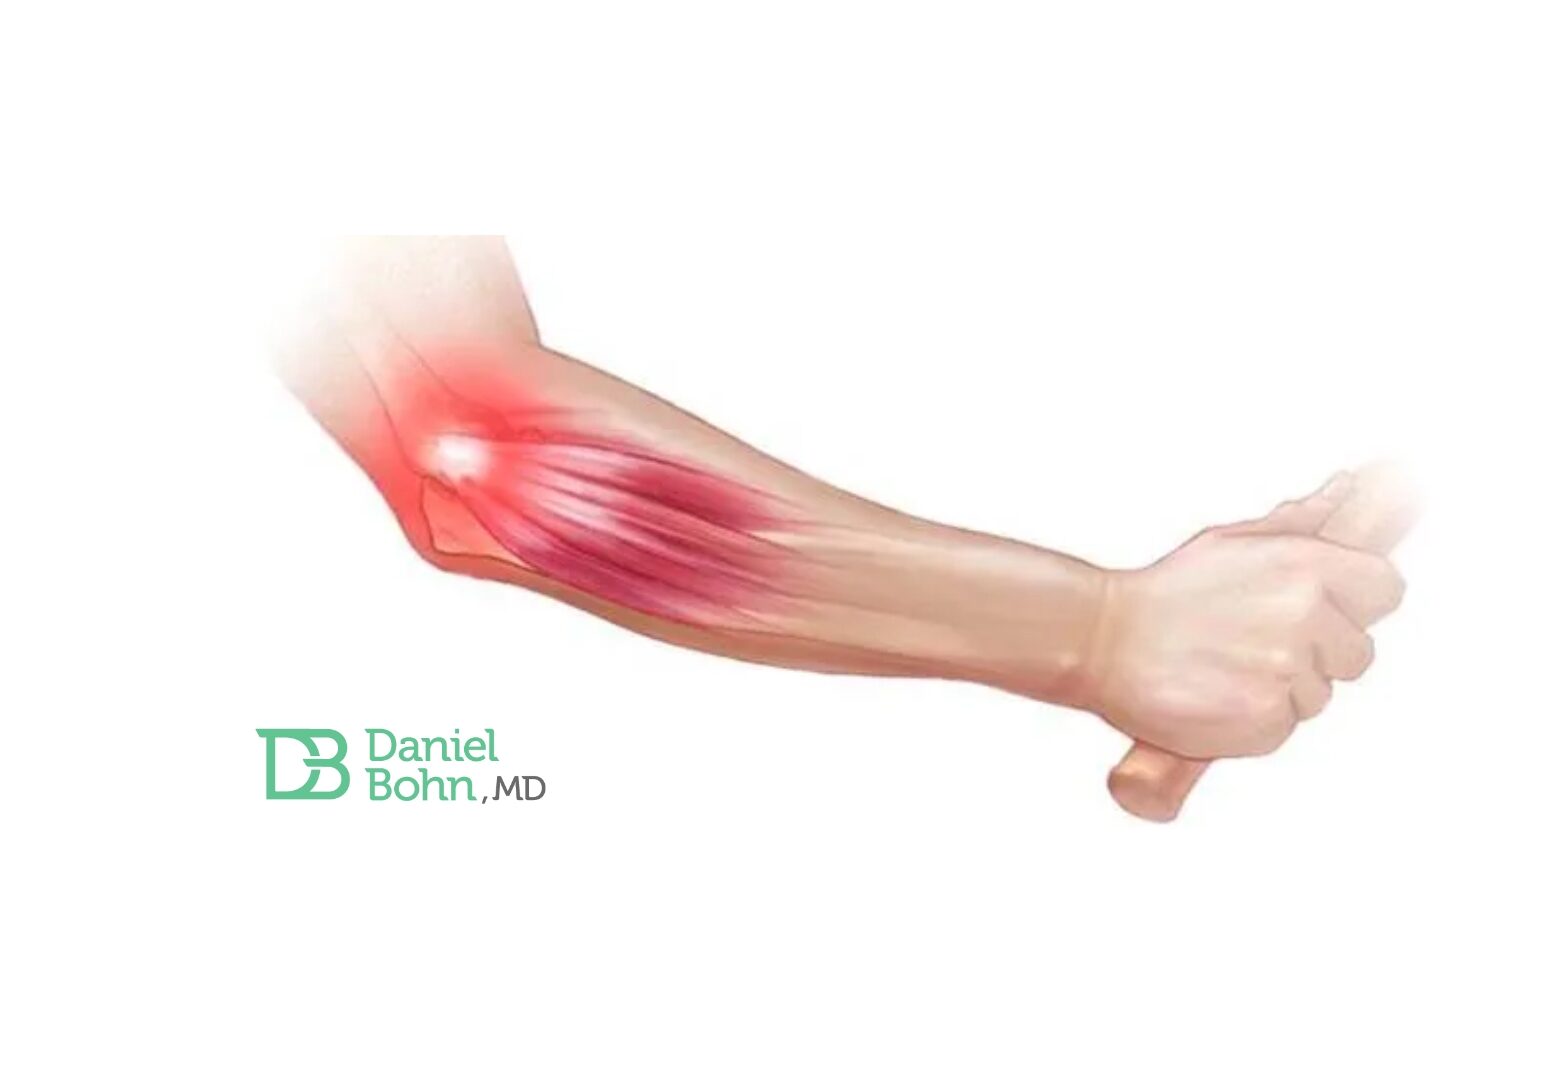

Principal motivo de consultas por dor no cotovelo. Entenda o motivo de ser ser tão comum (explicado pela anatomia): Uma das …